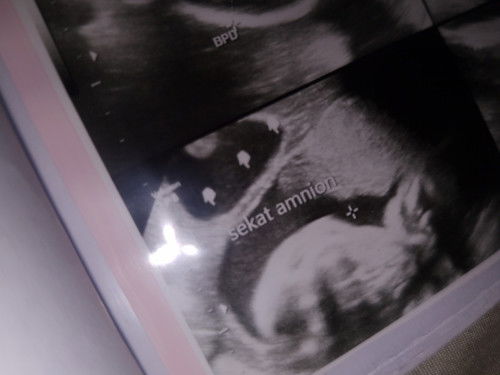

#seriusnanya ada yang begini juga ga bun hasil usg nya (amniotic band) ? Dan pas lahiran semua normal?